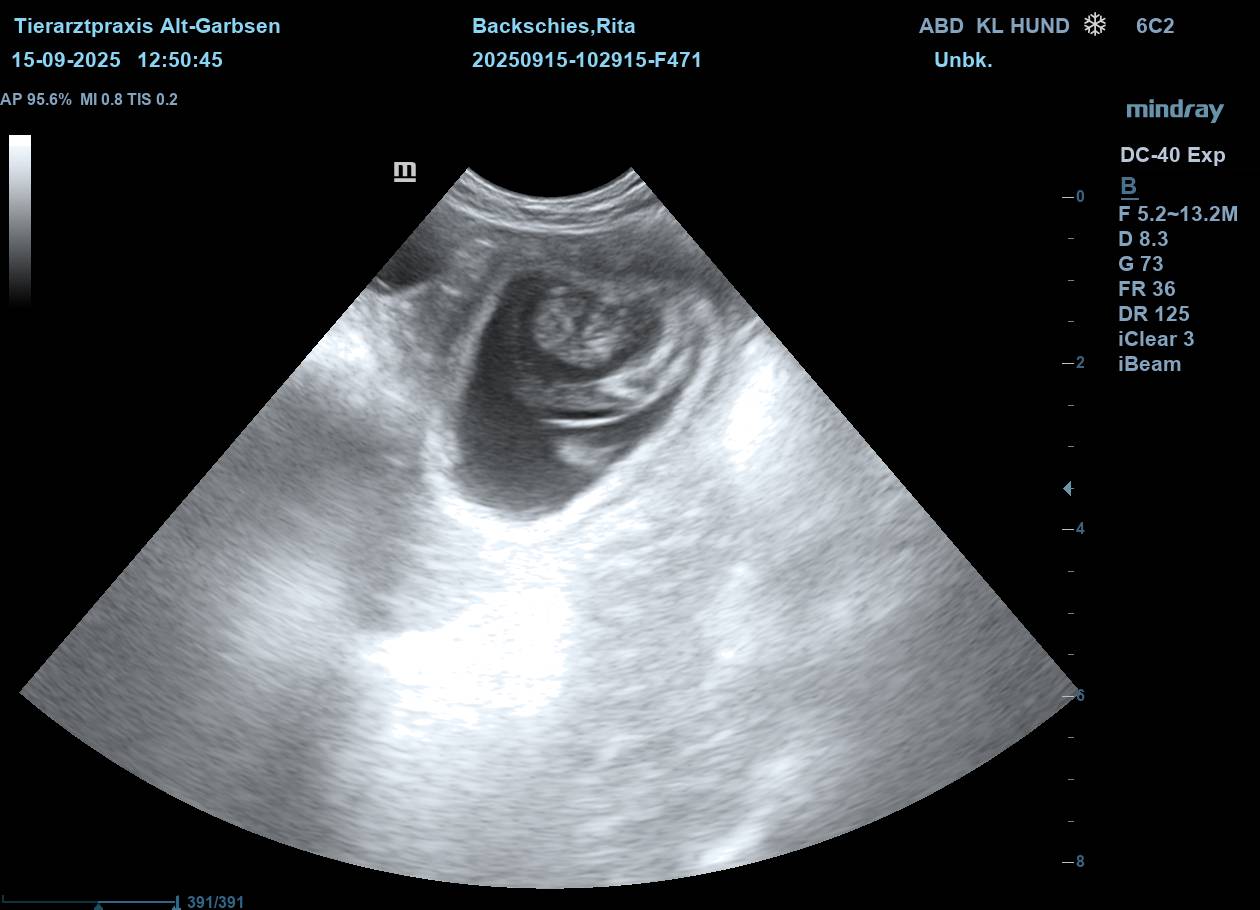

| Mo, 15.09.2025 | Es bahnt sich was an… der S-Wurf aus dem Zwinger Vom Lahberg FCI ist in die Produktion gegangen. Die Verpaarung am 17.08.2025 von Julissa Lisant Ingrid für Wambachtal „Rita“ und Kuddel vom Lahberg FCI war erfolgreich.🌿 Wir dürfen gespannt sein. In den nächsten Wochen werden wir dann Bilder vom wachsenden Babybauch posten. ![]() ![]() ![]() ![]() ![]() Jetzt heißt es mal wieder abwarten, beobachten, Däumchen drehen und hoffentlich bald freuen. |